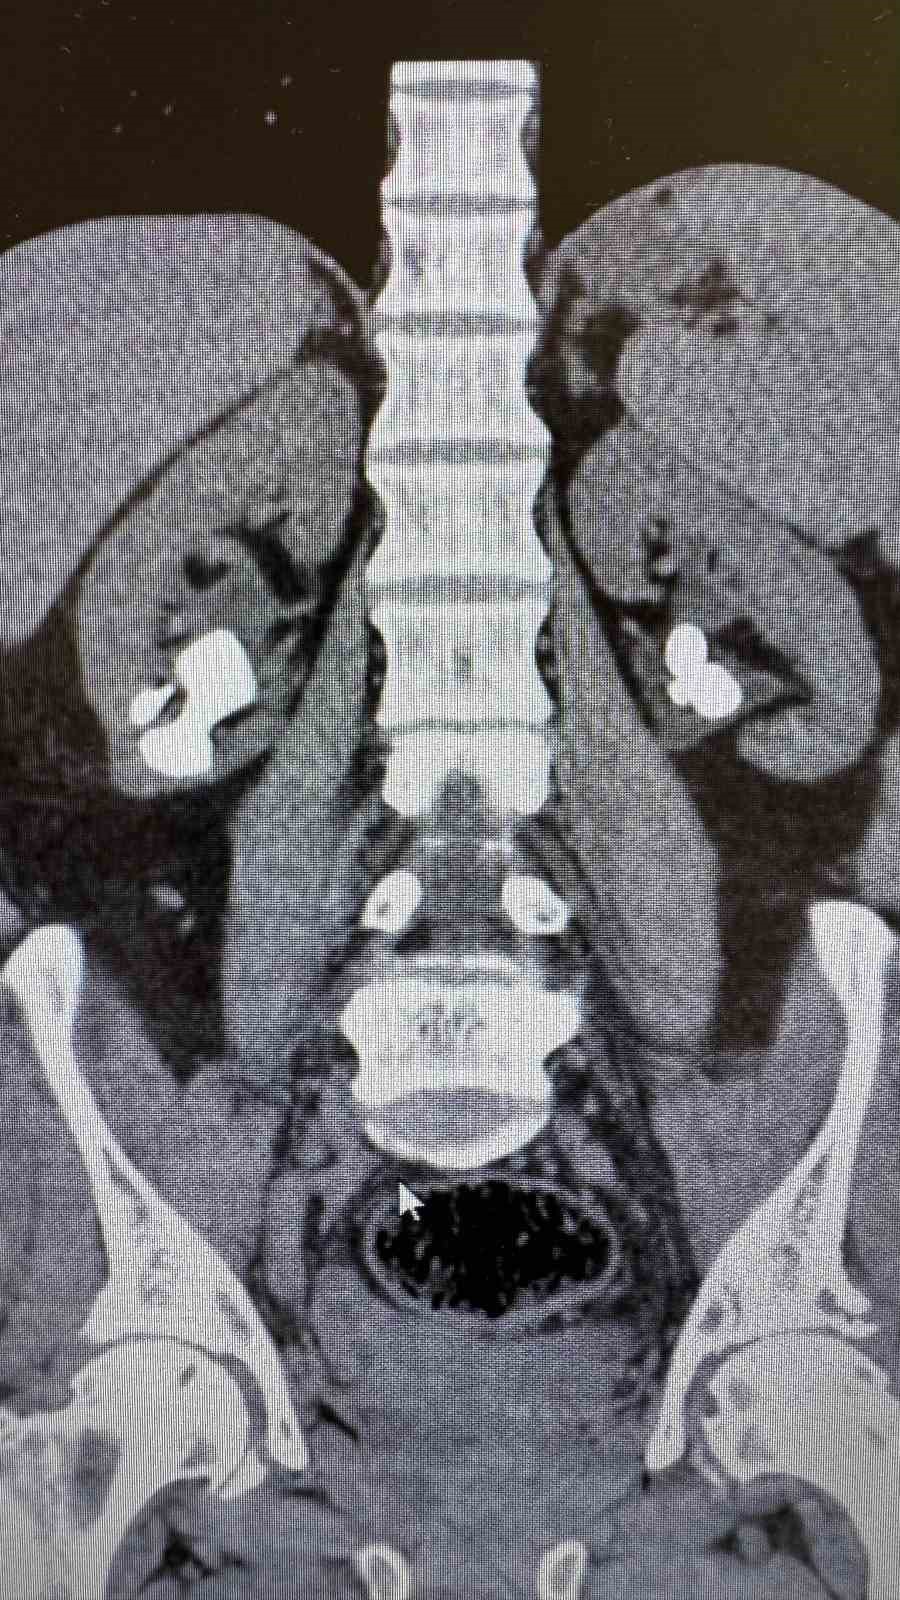

Üroloji Uzmanı Op. Dr. İlker Fatih Şahiner ve ekibince kapalı yöntemle (PNL) yapılan ameliyatlarda hastanın her iki böbreğindeki tekrarlayan sistin taşları temizlendi. Hastanın daha önce 10’un üzerinde böbrek taşı ameliyatı geçirdiği öğrenildi. Mayıs ayında yapılan ilk operasyonla sol böbrekteki taşlar alınırken, geçtiğimiz salı günü gerçekleştirilen ikinci operasyonla sağ böbrekteki taşlar da temizlendi.

Operasyonları gerçekleştiren Üroloji Uzmanı Op. Dr. İlker Fatih Şahiner, "Hastamızın her iki böbreğinde de tekrarlayan sistin taşları mevcuttu. Mayıs ayında sol böbreğine PNL yaparak taşsızlık sağlamıştık. Dün de sağ böbreğine PNL ameliyatını yaparak taşsızlık sağladık. Hastamızın genel durumu iyi, tedavisi servisimizde devam ediyor" dedi.